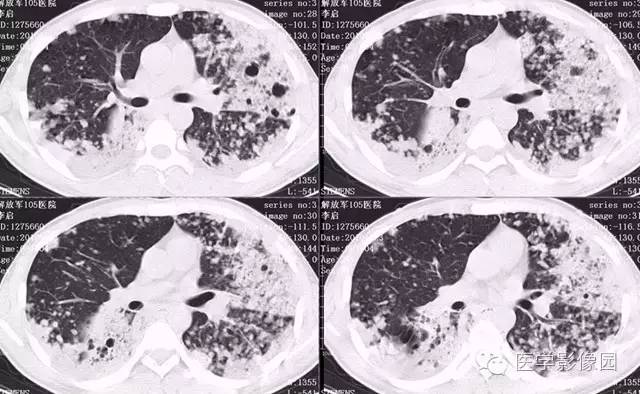

弥漫性肺泡细胞癌1例CT影像表现

病理结果:弥漫性肺泡细胞癌

弥漫性肺泡癌的主要临床及CT表现:临床表现无明显特征, 随着病情的进展, 咳嗽、 咳白痰、 进行性气促。CT表现 为病变分布有两种情况:病变累及一个肺段或肺叶;病变广泛分布于两肺。可归纳为5个特征性征象:蜂房征;支气管充气征;磨玻璃征;血管造影征;两肺弥漫分布的斑片状与结节影。